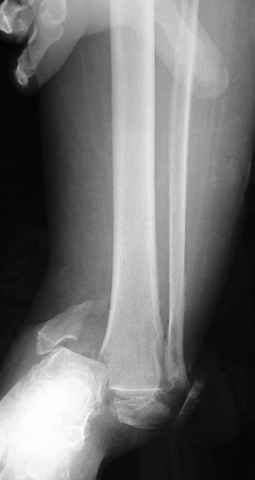

Re: ANKLE FRACTURE

Я вот все в толк не возьму смысл отдельной фиксации малоберцовой кости пластинкой, если все равно будет аппарат с фиксацией стопы, т.е. возможностью провести спицы в пятку, таран, наружную лодыжку и еще черт-те куда. Остеосинтез пластинкой выглядит логичным в случае, когда наружная фиксация планируется как временная. Но тут-то аппарат будет окончательным фиксатором.

I can't realize why plate fibula separately if anyway external fixator including the foot is planned, i.e. one may insert wires to the talus, calcaneus, lateral malleolus and anywhere else. Plating looks reasonable if only temporary ex-fix is planned, but in the case it will be definitive.